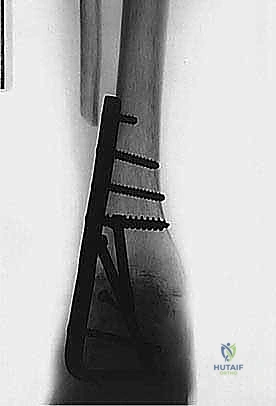

هنا تبرز الصفيحة النصلية (Blade Plate) كالحل الذهبي. تتميز هذه الصفيحة بوجود "نصل" صلب يتم إدخاله بقوة داخل عظمة الكعب، بينما يتم تثبيت الجزء الطولي من الصفيحة على عظمة قصبة الساق بالبراغي. هذا التصميم الهندسي يوفر مقاومة هائلة لقوى الانحناء والدوران، مما يضمن ثباتاً فورياً يسمح للعظام بالالتحام بشكل مثالي.

5. إدخال وتثبيت الصفيحة النصلية (Blade Plate)

هنا تكمن المهارة الجراحية الفائقة. يتم تشكيل مجرى دقيق داخل عظمة الكعب باستخدام إزميل خاص، ثم يتم طرق "نصل" الصفيحة المعدنية بحذر شديد داخل عظمة الكعب لضمان أقصى درجات الثبات.

6. التثبيت النهائي بالبراغي (Screw Fixation)

بعد التأكد من الموضع المثالي للصفيحة والنصل، يتم تثبيت الجزء العلوي من الصفيحة على عظمة قصبة الساق باستخدام براغي قشرية (Cortical Screws) قوية. يتم وضع العظام تحت ضغط ميكانيكي (Compression) لتحفيز الخلايا العظمية على الالتحام السريع.